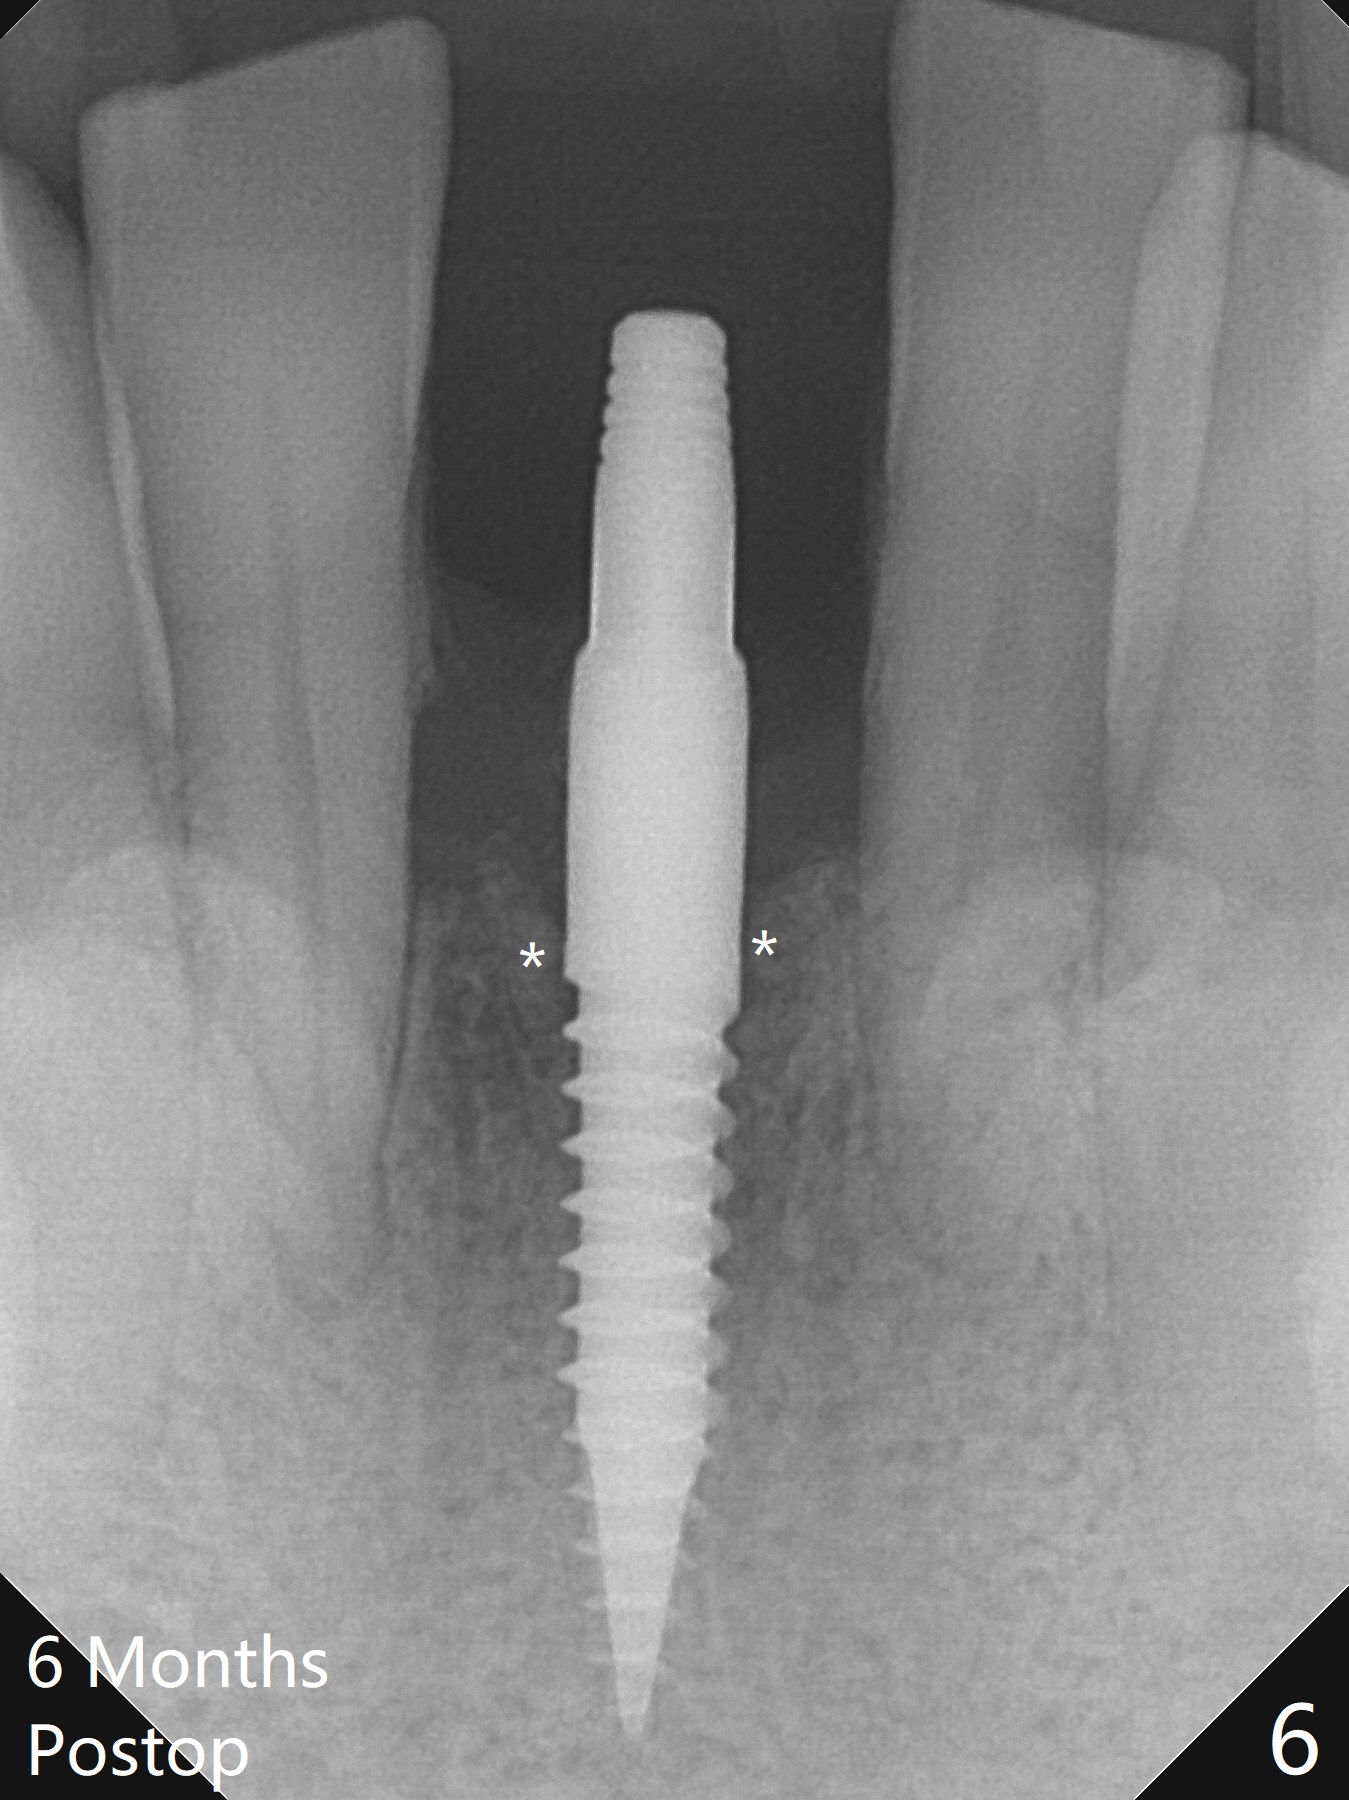

When the patient returns for implant placement 1.5 years after the last treatment (SRP), the tooth #25 has exfoliated, whereas the tooth #24 is severely displaced (Fig.1-3). In fact the buccolingual plates are found to be lost after extraction, corresponding to change in gingival color indicated by an arrowhead in Fig.1. Initial osteotomy with 1.2 mm drill is parallel to the terminal branches of the Incisive Canal (Fig.4 arrowheads). Since the gingiva is as thick as 7.5 mm (Fig.3 arrow), a 3x14 mm 1-piece implant with 4 mm cuff is placed (Fig.5); three implant threads are outside the native bone; with allograft (*) placed and the neighboring crests being coronal to the threads, the chance of periimplantitis should be remote. An immediate provisional is fabricated to contain the graft in place. Meanwhile the tooth #2 is symptomatic with crack. The top 3 threads appear to be contacted by the newly formed crestal bone 6 months postop (Fig.6 *). Bone appears to have grown into the space between implant threads 6 months post cementation (13 months postop).